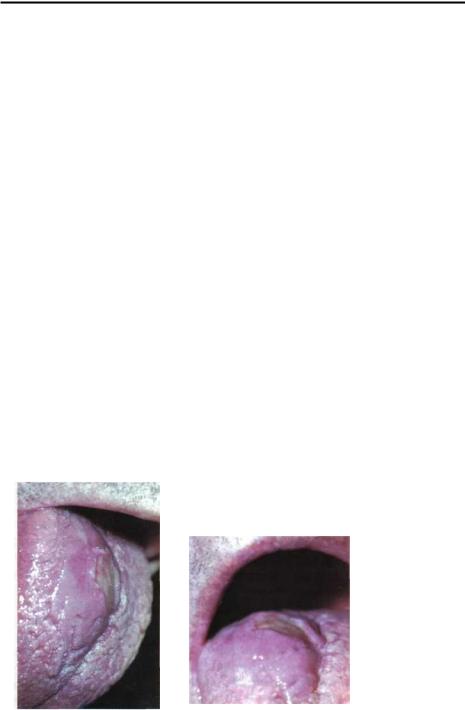

Глубокий бластомикоз. (Рис.3-6 и 3-7) Забо- |

Рис.3-6: |

Глубокийбла- |

Рис.3-7: Тоже - |

стомикоз языка. |

планом. |

рытыми краями и слизисто-гнойным отделяемым. В полости рта заболевание проявляется в виде одиночных, чаще множественных узлов, располагающихся в толще слизистой оболочки дёсен, языка, нёба и щёк. При дальнейшем распаде узла образуется язва с папилломатозными разрастаниями и хроническим течением; она может симулировать язвы гуммозного или бугоркового сифилиса, раковые язвы.